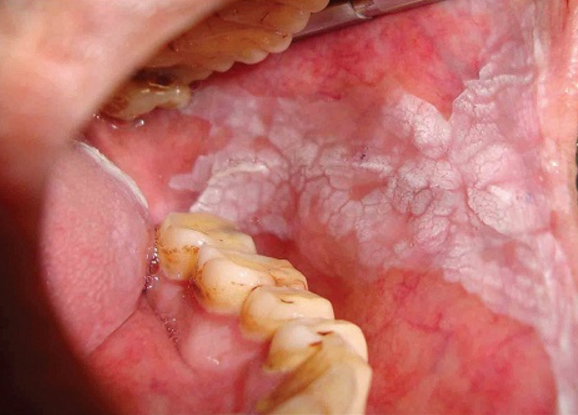

2Sores: Canker Sores, Herpes

Canker sores are not caused due to virus. They may occur due to common cold or might be plain hereditary in nature. They take around 12 days to disappear and most people allow it to take its own course of time. When it turns chronic, laser treatment can be an option to get rid of it. Herpes is caused due to a virus (Herpes Zoster) and is contagious through direct contact of the infected person. It affects the person by causing lessions and small blisters around the mouth and lips. There is no cure for this disease but it can be treated with antiviral pills and creams.